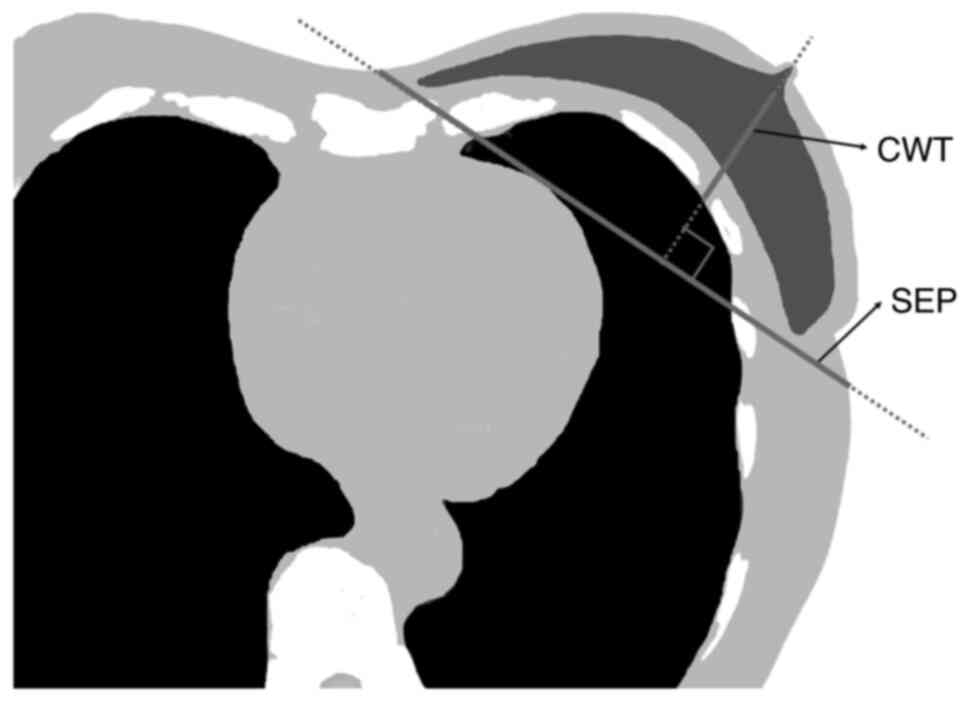

As explanatory variables, data including right-left, tumor site (upper-inner quadrant, lower-inner quadrant, upper-outer quadrant, lower-outer quadrant and central portions) (25), chest wall thickness (CWT), irradiation method (W, FIF-1RP and FIF-2RP), body mass index (BMI), separation (SEP), age, height and weight were collected retrospectively, whilst as an objective variable, MHD (12) was collected retrospectively. CWT and SEP were measured using a nipple-level one-slice simulated CT image for treatment planning (Fig. 1). SEP was defined as the distance along the posterior edge of the tangent fields at the nipple level. CWT was defined as the distance from the nipple surface to the lung, on a perpendicular line of breast separation. Data on the right and left sides, tumor site, irradiation method and BMI were collected from clinical records, whilst MHD was collected from the RT planning system. In the present study, MHD ≥300 cGy was defined as high MHD, whereas MHD <300 cGy would be defined as low MHD, following the QUANTEC cardiac guidelines (3). There were 76 patients (14%) of high MHD and 486 patients (86%) of low MHD.